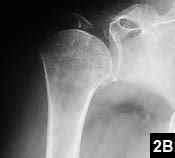

Varus displacement (varus and posterior shear). The spectrum of injury, clinical assessment and treatment robinson et al. Proximal humerus fx review references. Recognizing this fracture pattern and understanding the pathoanatomy of it are essential to providing appropriate care. @article{catalano2011valgusif, title={valgus impacted fracture of the proximal humerus.}, author={l. Dowling}, journal={the journal of hand surgery}, year={2011}, volume={36 11}, pages={. Proximal humeral fractures generally occur in older patients. These fractures are uncommon (<1% of proximal humeral fractures) 6. In this situation, the head is rotated into a valgus posture and driven down between the tuberosities. Humeral head replacement for severely displaced fractures of the proximal humerus was introduced the 1950s. We review the imaging, complications and management. A proximal humeral fracture can be a painful injury that limits your ability to move your arm and shoulder. Proximal humerus fractures with valgus deformity of the humeral head: Neer added this pattern rx as a separate category in 2002 rx. • radiographically will see alignment between medial shaft and head segments. Proximal humerus fractures account for 5% of all fractures of the appendicular skeleton. For pediatric patients see proximal humerus fracture (peds).